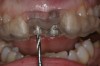

Figure 1  Initial presentation. Teeth Nos. 8 and 9 had internal and external resorption and were deemed hopeless. Recession of 4 mm was associated with tooth No. 9.

Figure 1